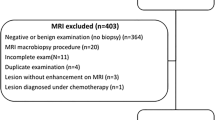

From February 2018 to November 2018, DCE MRI using CDTV was performed on 211 patients. The inline-generated parametric maps included Ktrans, kep, Ve, and IAUGC60. Histogram and texture features were extracted from the above parametric maps respectively based on a WL analysis. Student’s t tests, one-way ANOVAs, Mann-Whitney U tests, Jonckheere-Terpstra tests, and ROC curves were used for statistical analysis.